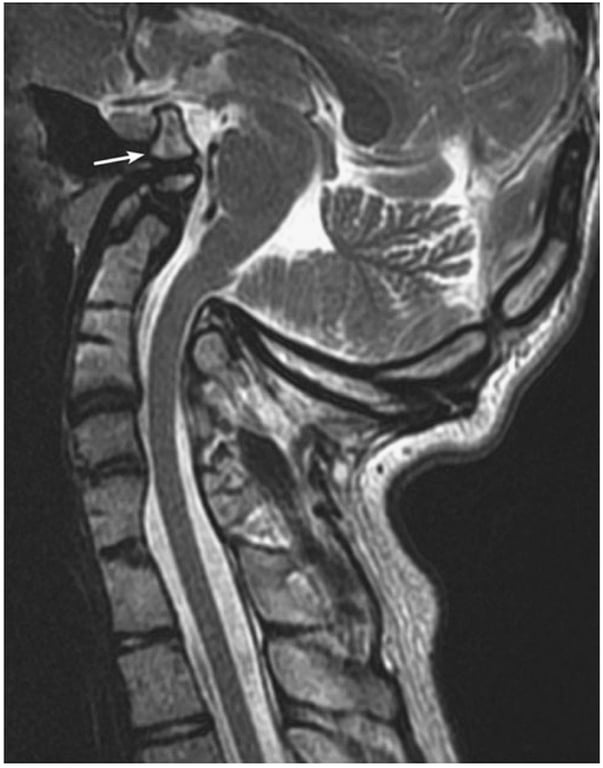

• Type II: BI + Chiari malformation.

• Odontoid tip tends to be above CL, but not McR or WCCL.

• Brainstem compression is due to reduced p-fossa volume.

• Patients older

• F:M= 1:1

• Less acute presentation

• Only 15% can be reduced with traction.

• Foramen magnum decompression is appropriate

Close-up of an x-ray of a brain AI-generated content may be incorrect.